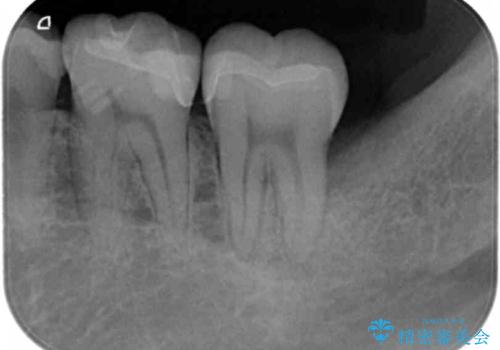

- 長年気になっていた銀歯を白く、自然にしたいと希望され来院されました。

銀歯を丁寧に除去し、内部に虫歯の再発がないかどうか拡大鏡下で確認した上で、精密に封鎖することのできるセラミックインレー治療を計画します。